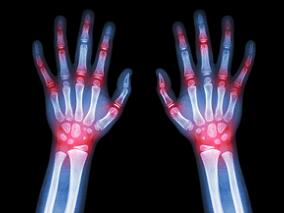

女性RA患者早期体重变化也会影响死亡率?

1小时条评论2018年1月,发表于《Arthritis Rheumatol》上的一项研究,考察了风湿性关节炎(RA)女性患者和匹配的对照者中,早期RA中的体重变化和随后的死亡风险。 目的:考查早期RA中的体重变化是否与随后的死亡相关,并评估是否有RA特定影响。 方法:研究者确定了在护士健康...

降低RA患者心血管结局风险:外用or口服非选择性NSAIDs

1小时条评论2017年10月,发表在《J Am Heart Assoc》的一项由美国和台湾科学家进行的研究比较了台湾类风湿性关节炎(RA)患者中,外用和口服非选择性NSAIDs的心血管结局风险。 背景:外用NSAIDs的全身吸收效果不及口服NSAIDs。研究者考察了台湾RA患者中,与非选择性外用NSAIDs ...

靶点治疗策略能否改善RA患者的缓解率?

1小时条评论2017年11月,发表在《Health Technol Assess》上的一项系统评价,对类风湿关节炎(RA)靶点治疗(TTT)策略的临床有效性以及成本效果进行了考察。 背景:对于RA患者的治疗,TTT是一个宽泛的概念。其包括设定一个治疗靶点,通常是缓解或降低疾病活动程度(LDA)。其...